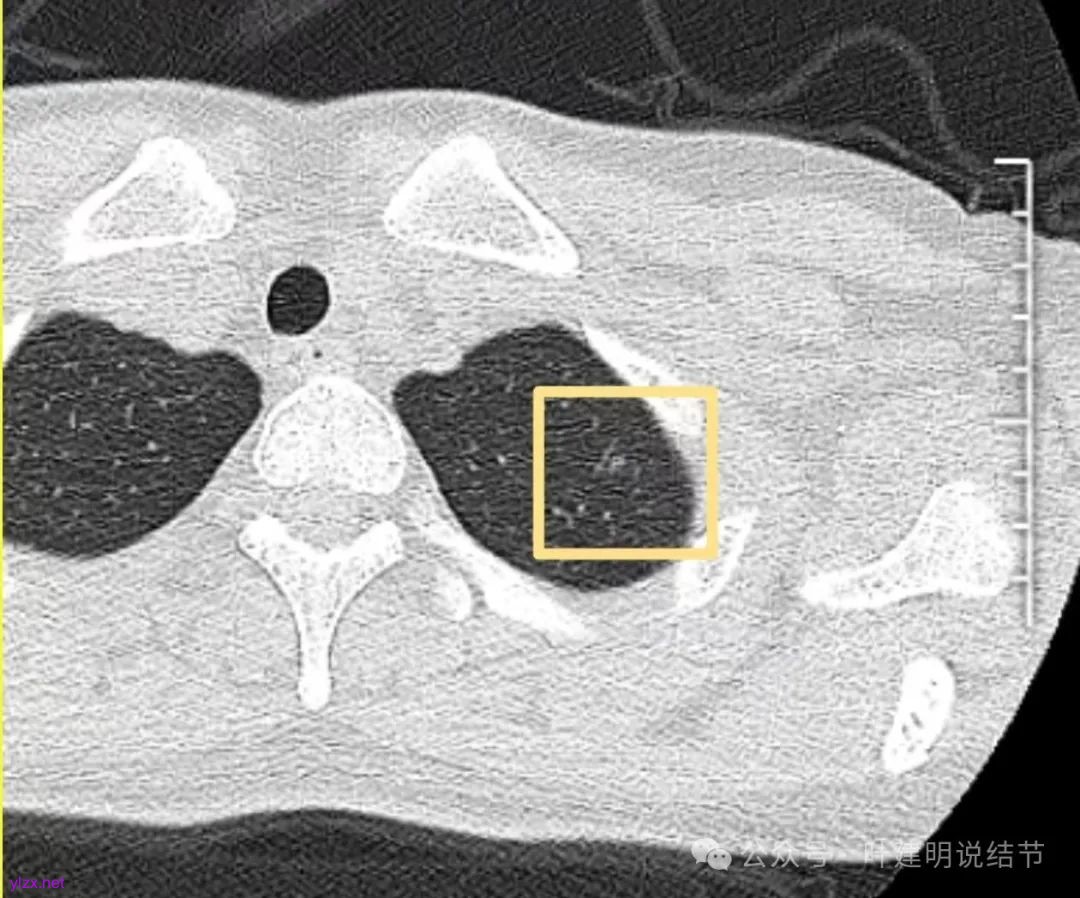

先来看2024年12月的影像:

左上叶淡而轮廓欠清楚的磨玻璃结节,缺乏聚拢性,没有收缩力。

再看2022年9月的影像:

右下当时是很淡的,也显偏模糊的磨玻璃影。

怎么有个点状密度较高的结节在?与上面那截图的淡磨并不完全在一块的。

密度甚高,边界与轮廓清楚,只看这真的不像恶性些。

边缘区也瘤肺界限稍糊,整体轮廓还行。有进展的是不是就是淡磨那处?

两肺多发结节,左侧黄色标注的考虑是肺泡上皮增生可能性大;蓝色的考虑肺泡上皮增生或者少许慢性炎可能性大;右侧红色宽起来并带有红色箭头的这处是主病灶,偏混合密度,整体轮廓较为清楚,边缘显得毛糙,从2024年12月份的来看,要考虑是肿瘤范畴,原位癌或者微浸润性腺癌可能性较大,也不能完全排除不典型增生。但是在2022年的时候,这个病灶的边上也有一个实性的微小结节,如果只看2022年的,这么小的实性结节,又比较圆,表面也显得较为光滑,是要考虑良性的,当然太小了需要动态观察。回头再重新来看2024年底的,发现绿色箭头所指的这个微小实性的较2022年几乎没有变,去仔细寻找2022年的,发现当时在实性结节旁边也有密度很淡的一点磨玻璃影(也可能真的就是一处,只是扫描不够薄,密度的变化有些突兀而已),而到了2024年12月份,实性微小这处没有明显变化,但是原来很淡的磨玻璃变成了混合磨玻璃,范围也明显扩大。所以总体来看右肺下叶这处是考虑恶性的,而且从磨玻璃结节角度来讲,还是生长比较快的,就是说还是有一定风险的。加上左侧还有两处也是磨玻璃持续存在,虽然边缘轮廓显模糊一点,但多年以后也可能仍然要变成原位癌或者微浸润性腺癌之类的东西。通盘考虑以后,我倾向于右侧近期单孔胸腔镜下微创局部切除,左侧随访观察,等到有进展并风险增加再来考虑处理。意见供参考!